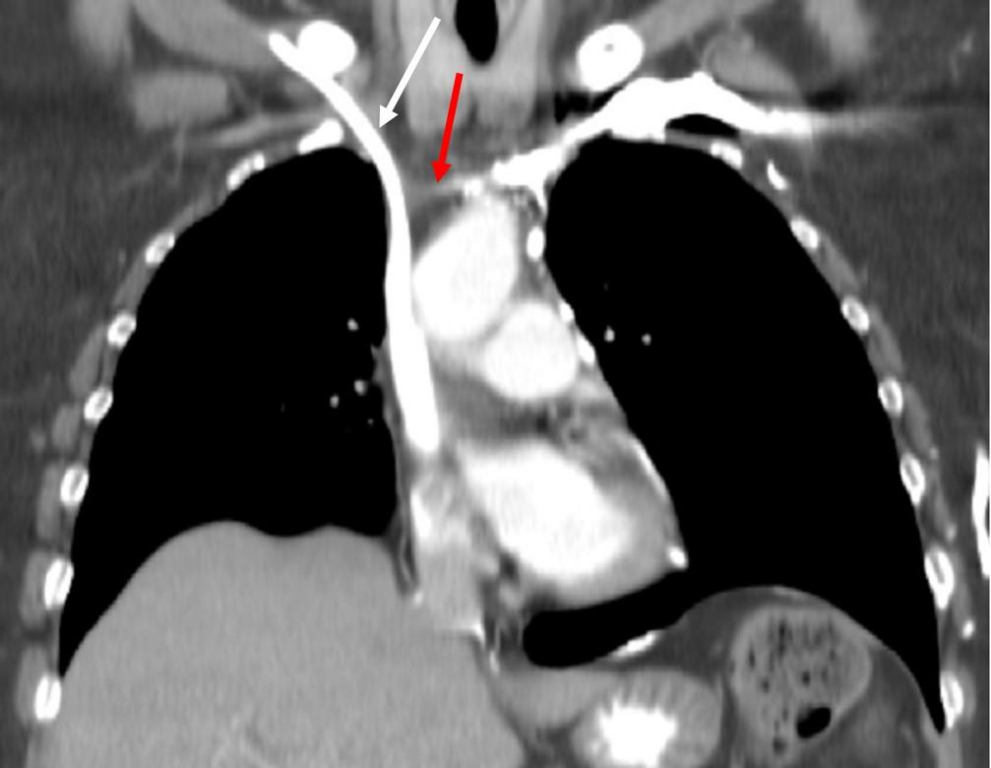

对比增强冠状重建 CT 图像显示闭塞的左无名静脉(红色箭头)。

右侧无名静脉插入了一条化疗导管(白色箭头)。